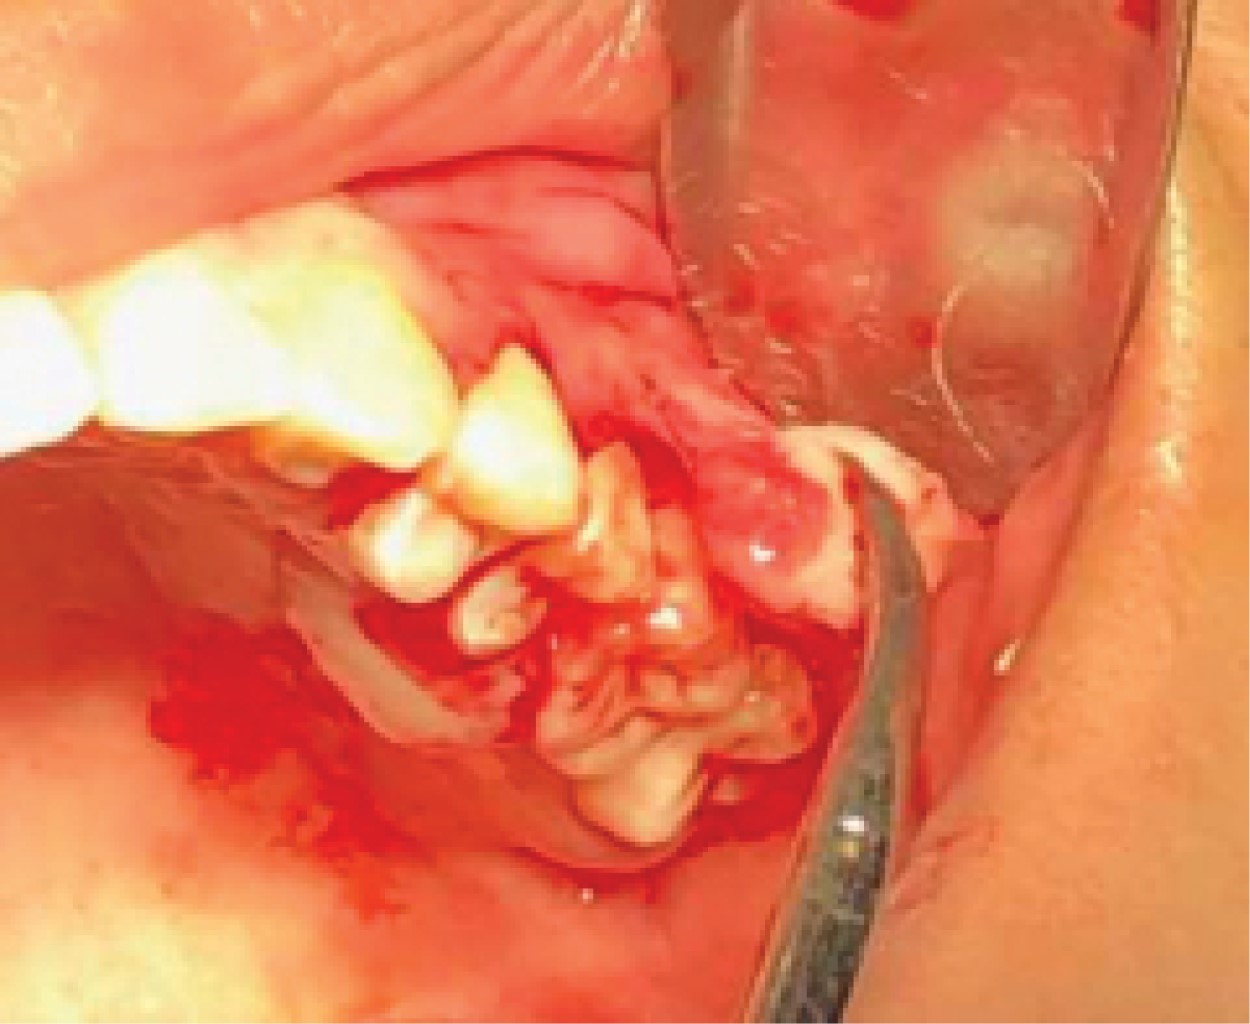

Figure 4